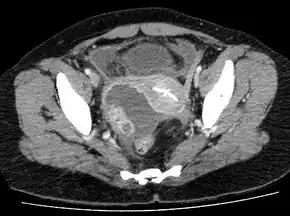

There maybe yellow-green discharge seen from the cervix and it may hurt when the cervix is moved.[2] Blood tests usually reveal an elevated white blood cell count.[2] Other tests may include pregnancy test; culture of urine, cervical discharge, and blood; as well as a wet mount of vaginal discharge for clue cells.[2] Medical imaging, such as ultrasound, CT scan, or MRI, will often show the abscess.[2] Treatment is initially with antibiotics given by injection.[2] Drainage via needle aspiration, laparoscopy or laparotomy, may be carried out if this is not effective.[2] Generally hospitalization is required.[3]

Laparoscopy and other imaging tools can visualize the abscess. Physicians are able to make the diagnosis if the abscess ruptures when the woman begins to have lower abdominal pain that then begins to spread. The symptoms then become the same as the symptoms for peritonitis. Sepsis occurs, if left untreated.[15]: 103 Ultrasonography is a sensitive enough imaging tool that it can accurately differentiate between pregnancy, hemorrhagic ovarian cysts, endometriosis, ovarian torsion, and tubo-ovarian abscess. Its availability, the relative advancement in the training of its use, its low cost, and because it does not expose the woman (or fetus) to ionizing radiation, ultrasonography an ideal imaging procedure for women of reproductive age.[8]